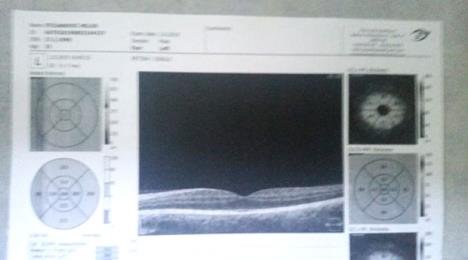

Pored teških bolova koje trpeo sve ove godine nedavno mu je otkriveno i zamućenje u staklastom delu oka. Terapija koja uključuje lekove i kapi za oči je jako skupa, dok je za operaciju u Srbiji potrebno između 400 i 500 evra. Ove tegobe prati i otežano kretanje, kao i hematom u nozi.

Nalazi lekara